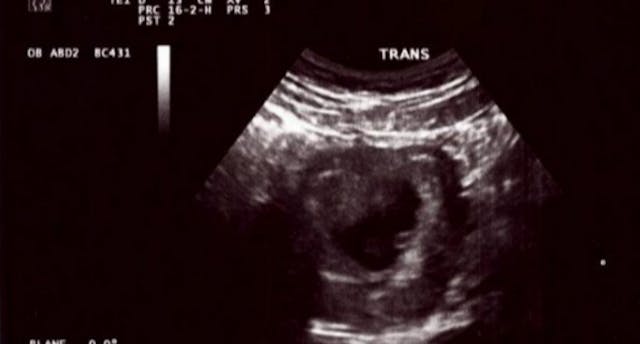

As they approached the abortion clinic, they noticed a blue mobile unit across the street advertising free ultrasounds. A nurse named Rosie stopped them and asked if they’d like to receive one. Since Sofia wasn’t sure how far along she was at this point, she agreed. Kory and Sofia both loved the Stork Bus and felt safe getting the ultrasound done in its organized and clean environment. When they saw their little baby of only 7.3 weeks on the screen, Kory started to cry thinking about what would have happened had they chosen the abortion clinic that day.

Rosie played the heartbeat for the couple and they were amazed that a person so small had such a very loud heartbeat. Sofia and Kory knew at that moment that they were going to be parents and had no need to visit the abortion clinic across the street. Little Zoe was born on March 16, 2015 weighing in at only 6 lbs and 4 oz.